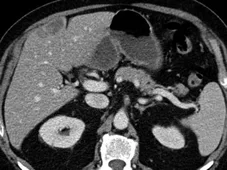

Figure 3. Métastases hépatiques d’un cancer du colon.

A. Examen initial montrant que le grand axe de la lésion est de 81 mm.

B. Après quatre cycles de chimiothérapie, la lésion mesure 59 mm, soit une amélioration de 27 %. Bien que la lésion ait visuellement diminué de façon évidente, il ne s’agit pas encore d’une réponse partielle, car le cap des 30 %

de diminution n’est pas franchi. La réponse est classée « SD »